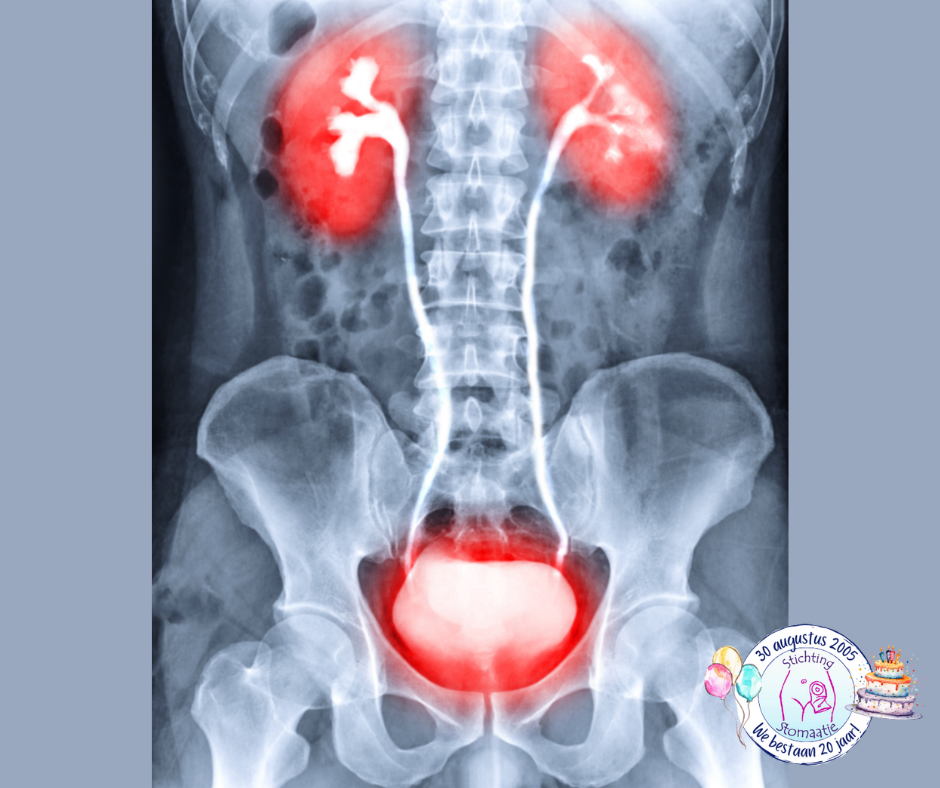

Intra Veneus Pyelogram (IVP)

Bij dit röntgenonderzoek wordt er gekeken naar:

- de nieren (renes)

- de urineleiders (ureters)

- de blaas (vesica urinaria)

De darmen moeten schoon zijn, omdat er anders een mogelijkheid bestaat dat een gedeelte van de nieren en/of urineleiders niet goed op de foto te zien zijn. Door middel van een injectie via een bloedvat in de arm, wordt een jodiumhoudend contrastmiddel toegediend waarna er foto's worden gemaakt. Mogelijke bijwerkingen/risico’s zijn een allergie voor jodiumhoudend contrast, extra voorzichtigheid bij verminderde nierfunctie en het belang van goed drinken na afloop. In de praktijk wordt IVP steeds vaker vervangen door een CT-scan van de urinewegen (CT‑IVP of CT‑urogram).

Cystogram